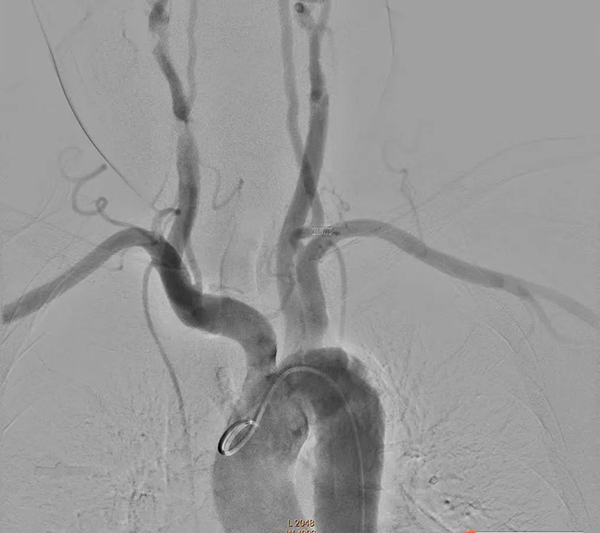

在市十院介入科团队、神经内科团队和医大二院神经外科团队共同努力下手术非常顺利,术中选用5F猪尾造影管开始进行主动脉弓造影和旋转造影见椎动脉V4段动脉瘤。选取工作角度,应用导丝超选至基底动脉,选用3.5*20mm pipeline II支架,定位释放。术后造影显示瘤体内血流灌注延迟缓慢。

主动脉弓造影